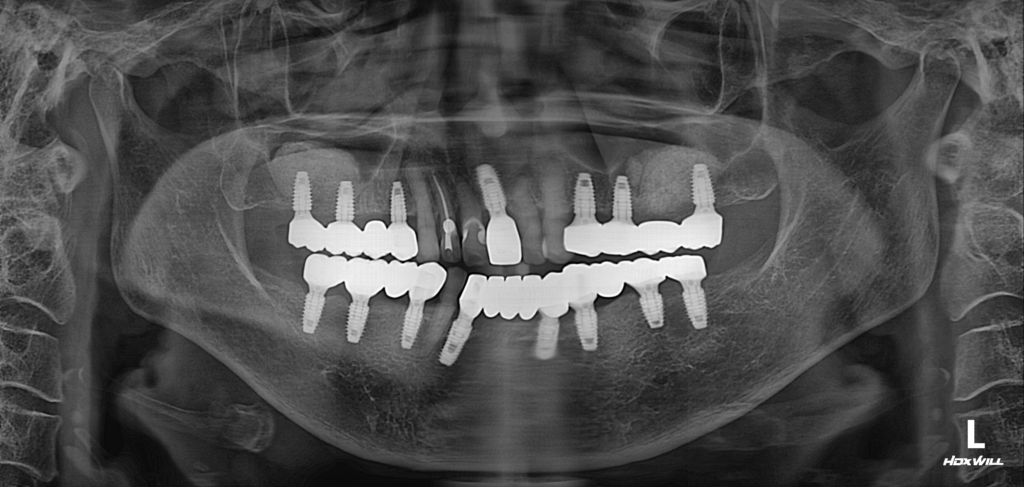

술후 사진

2023.02.02

하악 전치부는 강한 저작력이 요구되는 부위가 아니기 때문에, 필요한 부위만 최소한으로 임플란트를 식립하여 심미적 균형을 우선적으로 맞추었습니다.

반면 상·하악의 구치부는 저작 기능을 책임지는 핵심 부위이므로 가능한 한 치아와 임플란트를 1:1 비율로 배치하여 충분한 저작력을 지지할 수 있도록 설계했습니다. 큰 힘을 받는 대구치 부위는 소구치보다 더 높은 저작력이 필요하기 때문에, 정밀한 위치 선정과 정밀한 식립을 통해 안정적인 기능 회복을 목표로 진행하였습니다.